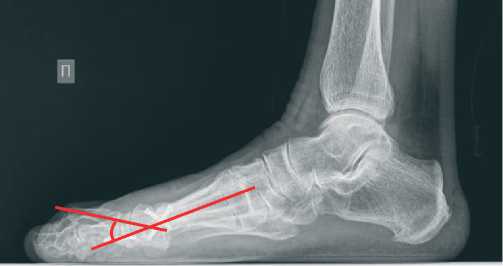

По данным стандартной рентгенографии стопы угол hallux valgus (М1Р1) исходно равен 45 градусов (Рисунок 2), угол ТО второго пальца – 45 градусов (Рисунок 3).

Рисунок 3. Исходные данные рентгенографии правой стопы в боковой проекции

По рентгенограмме в прямой проекции было подтверждено полное устранение hallux valgus (угол М1Р1= 7 градусов) (Рисунок 5). На снимке в боковой проекции угол ТО был равен 30 градусов (Рисунок 6).

Рисунок 6. Данные рентгенографии правой стопы в боковой проекции через 1 год после операции